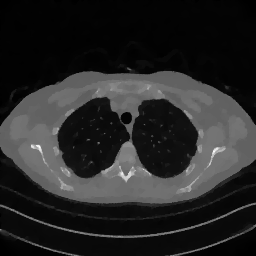

2.1 Experiments on a synthetic image

To analyze the behavior of the proposed weighting scheme for different choices of 𝒙~~𝒙\tilde{\boldsymbol{x}}over~ start_ARG bold_italic_x end_ARG, we conduct a simple experiment involving sparse CT reconstruction using a synthetic image, shown as the first image in Figure 3. We denote as 𝒙GTsuperscript𝒙𝐺𝑇\boldsymbol{x}^{GT}bold_italic_x start_POSTSUPERSCRIPT italic_G italic_T end_POSTSUPERSCRIPT this synthetic ground truth which incorporates structures commonly encountered in tomographic imaging: homogeneous regions with regular shapes simulating tumoral masses, high-density areas representing bones or metallic implants, and objects with extremely thin edges.

The corrupted measurement 𝒚δsuperscript𝒚𝛿\boldsymbol{y}^{\delta}bold_italic_y start_POSTSUPERSCRIPT italic_δ end_POSTSUPERSCRIPT is then computed by simulating projections from the ground truth image 𝒙GTsuperscript𝒙𝐺𝑇\boldsymbol{x}^{GT}bold_italic_x start_POSTSUPERSCRIPT italic_G italic_T end_POSTSUPERSCRIPT, according to the image formation model in Equation (1.1) using a fan-beam scanning geometry with only 45 projections uniformly distributed over the angular range [0,180]0180[0,180][ 0 , 180 ]. The noise 𝒆𝒆\boldsymbol{e}bold_italic_e is obtained by sampling 𝒛𝒩(𝟎,𝑰)similar-to𝒛𝒩0𝑰\boldsymbol{z}\sim\mathcal{N}(\boldsymbol{0},\boldsymbol{I})bold_italic_z ∼ caligraphic_N ( bold_0 , bold_italic_I ) and computing:

We conducted two simulations with different noise intensity, setting ν=0.005𝜈0.005\nu=0.005italic_ν = 0.005 and ν=0.02𝜈0.02\nu=0.02italic_ν = 0.02. For all the experiments, we have chosen η=2105𝜂2superscript105\eta=2\cdot 10^{-5}italic_η = 2 ⋅ 10 start_POSTSUPERSCRIPT - 5 end_POSTSUPERSCRIPT. Regarding the regularization parameter λ𝜆\lambdaitalic_λ, we have assigned consistent heuristic values across all weighted methods. To validate the selections of the space-variant parameters, we compare the results obtained using the proposed adaptive weighted TV model (2.2) method with those derived from global TV regularization (1.3) (the value of the regularization parameter λ𝜆\lambdaitalic_λ has been adequately set ad hoc for the global TV). We briefly present the results of this simulation, which firstly demonstrate the effectiveness of the proposed weights and subsequently confirm that setting 𝒙~=𝒙GT~𝒙superscript𝒙𝐺𝑇\tilde{\boldsymbol{x}}=\boldsymbol{x}^{GT}over~ start_ARG bold_italic_x end_ARG = bold_italic_x start_POSTSUPERSCRIPT italic_G italic_T end_POSTSUPERSCRIPT yields a highly accurate reconstructed image.

These findings are further confirmed by Figure 3, which presents a cropped view of the restored images in the case ν=0.02𝜈0.02\nu=0.02italic_ν = 0.02. Clear differences in the outputs are noticeable, particularly in the reconstruction of finer cross details and contrast. Notably, the global TV method consistently fails to reconstruct the cross, regardless of the parameter settings. The superior reconstruction performance achieved when 𝒙~=𝒙GT~𝒙superscript𝒙𝐺𝑇\tilde{\boldsymbol{x}}={\boldsymbol{x}}^{GT}over~ start_ARG bold_italic_x end_ARG = bold_italic_x start_POSTSUPERSCRIPT italic_G italic_T end_POSTSUPERSCRIPT highlights the effectiveness of adapting regularization to image pixels when a highly accurate approximation of the target image is available. Figure 3 also includes the plot of the relative error, where the relative position of the curves is maintained across all iterations, consistently with the behavior discussed in Table 3. The plots clearly demonstrate that the error stabilizes, suggesting that a stationary point has been achieved for each method. We specify that the graphs display the executions carried out with 10000 iterations of the Chambolle-Pock method to analyze the behavior until convergence, whereas the images visually show no further changes after a few hundred iterations.

Figure 3: Results of the experiment on the synthetic image with higher noise (ν=0.02𝜈0.02\nu=0.02italic_ν = 0.02). In the first row, from left to right: the entire ground truth image with a red square depicting the crop of interest, cropped zooms on the reconstructions by GT-W1𝑊subscript1W\ell_{1}italic_W roman_ℓ start_POSTSUBSCRIPT 1 end_POSTSUBSCRIPT, FBP-W1𝑊subscript1W\ell_{1}italic_W roman_ℓ start_POSTSUBSCRIPT 1 end_POSTSUBSCRIPT, TV-W1𝑊subscript1W\ell_{1}italic_W roman_ℓ start_POSTSUBSCRIPT 1 end_POSTSUBSCRIPT and by the global TV model. In the second row: plot of the Relative Error over the iterations.